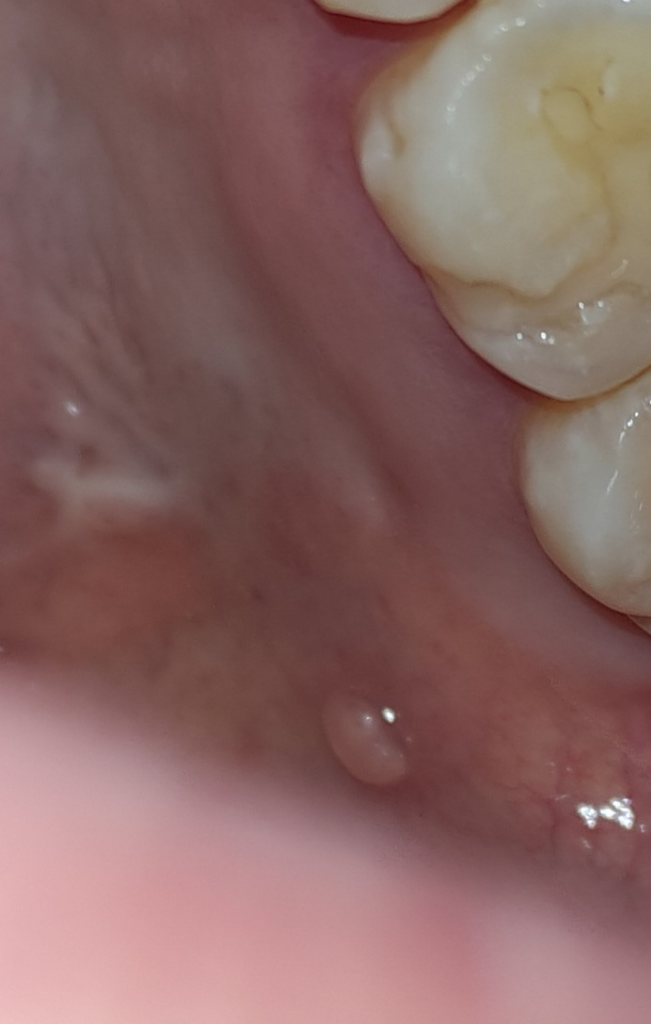

입천장에 계속 여드름이 나요?

3개월전부터 계속 입천장에 여드름이나요

생겻다가 터져서 없어졌다가 반복이에요

왜그럴까요 2월에 사랑니 뽑았었고

• 1번 째 사진

입천장 여드림이라기보다는 해당 부위 주변 치아 뿌리에 염증이 생겼을 가능성이 매우 높습니다. 즉 염증이 계속해서 생기게 되어 해당 염증이 치조골을 녹이고 외부로 개통되어 나오는 것으로 보여지며 이를 sinus tract이라고 부르게 됩니다. 따라서 지금 상태라면 치아에 대한 평가를 받아보시고 적절한 치료를 하셔야 합니다.

사진을 찍어봐야 알겟지만 대부분 저런경우는 치아 뿌리에 염증이 잇어서 그럴가능성이 높습니다. 만약 치아 뿌리 염증이라면 신경치료를 하셔야될수도 잇습니다.